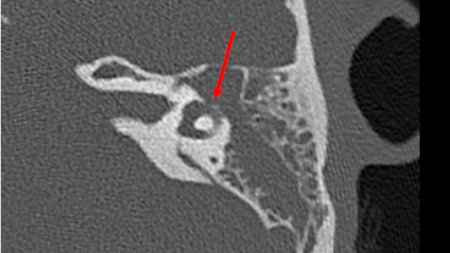

An axial CT (without contrast) of the temporal bone of the left ear demonstrating direct erosion into the horizontal semicircular canal by cholesteatoma

From the personal collection of Dr Tiffany Hwa; used with permission